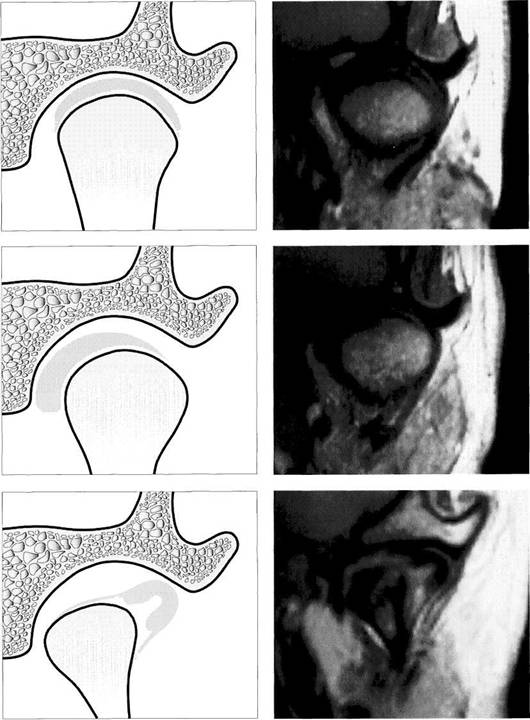

Degenerative joint changes (from Hatcher and Lotzmann 1992)

Radiographic representation of joint surface changes has two sig­nificant disadvantages:

Stages A through C

In these stages the joints appear normal in radiographs (panoramic radiograph, Schuller projection, to­mogram, CT). A Physiological joint with normally

functioning articular surfaces. B Progressive adaptations are ex­pressed as thickenings of the fi-brocartilage that cannot be seen on the radiograph or diagnosed clinically.

C Overloading leads to flattening ofthefibrocartilage.

Stages D through F

D With further chronic overload­ing of the articular surfaces, car­tilage matrix is resorbed and the contour of the bony condyle be­comes flatter. Clinically, slight grating sounds arise at this point.

E With increased loading the joint surfaces become deformed and the bone contours are flattened even more.

F If sufficient adaptation occurs, fibrocartilage will compensate for the osseous changes. Other­wise the rubbing sounds in­crease in intensity.

377 Stages G through I

Signs of chronic overloading of the

joint surfaces that are always visible

in the radiograph:

G Formation of a lip at the anterior border.

H Breaking off of free bodies with­in the joint.

I    Formation of subchondral cysts.

Even advanced stages of osseous joint surface changes can some­times become perfectly adapted through the formation of fibrocarti­lage. These cases usually have no clinical symptoms and therefore do not require treatment.